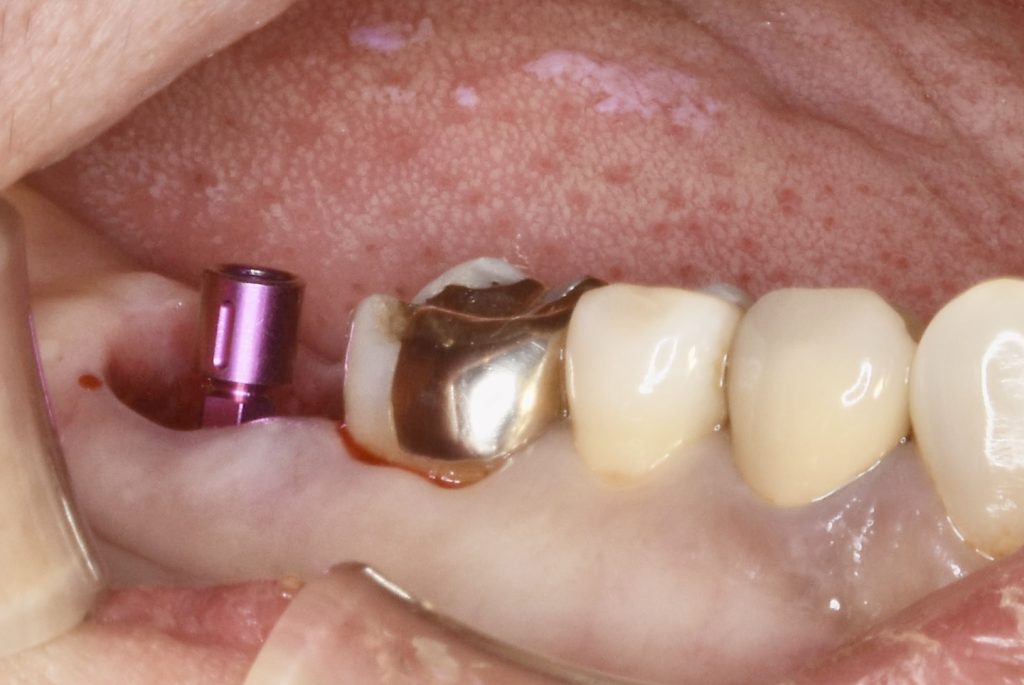

今回、古いメタルインレーの中でカリエスが進行し、骨縁下まで進行していました。

抜歯と同時にインプラント埋入手術を行い、4ヶ月ほどで治療を完了いたしました。